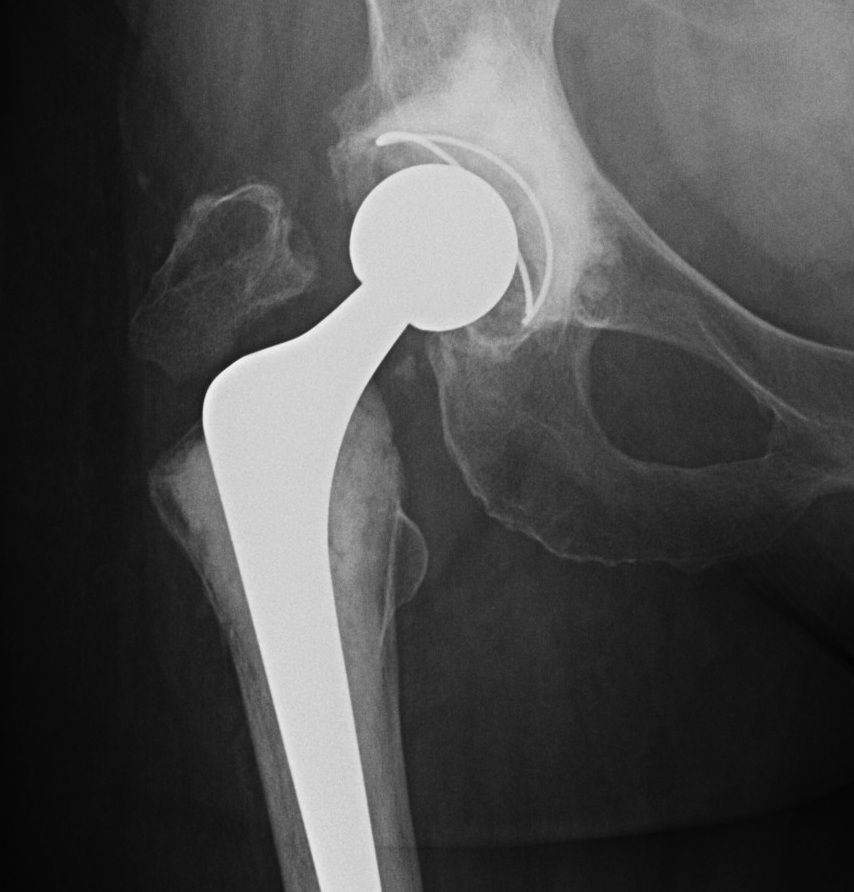

Fracture with stem subsidence around a polished tapered femoral stem treated with ORIF